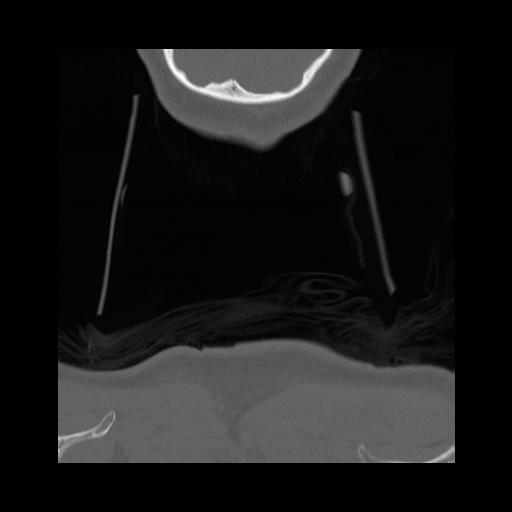

16 HUESO,,Coronal,2.000,HUESO,Coronal,